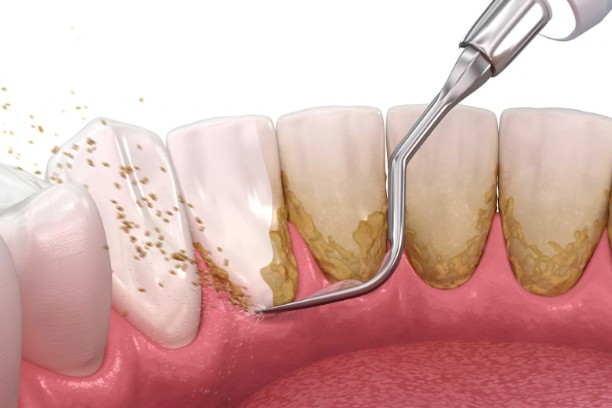

SCALING AND ROOT PLANNING

SCALING AND ROOT PLANNING